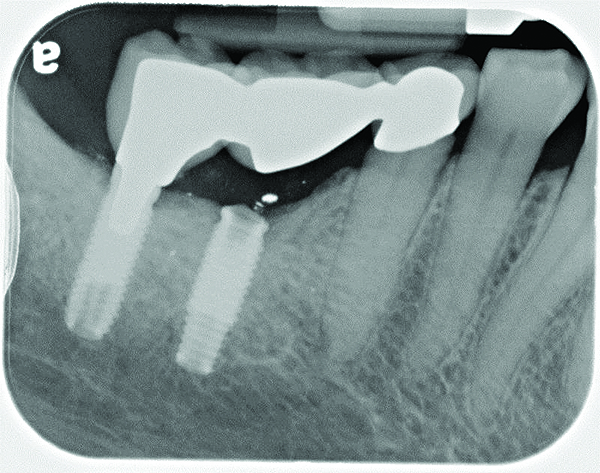

Maxillary right lateral incisor implant restoration with severe bone and soft tissue loss is classified a major complication which may not be completely reversible.

Figure 5

Computerized axial view of the implant in Fig 5 showing the buccal bone loss and exposed implant surface.

Figure 6